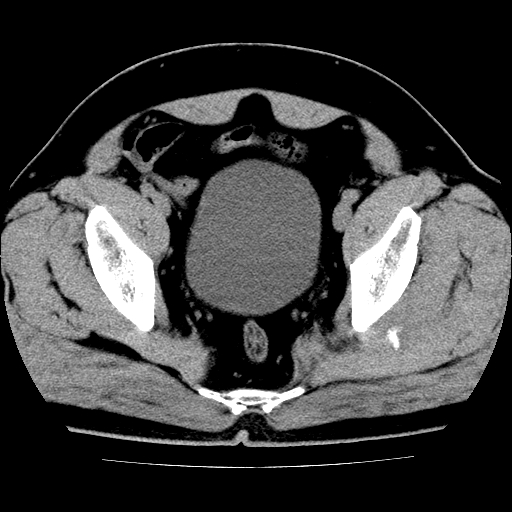

标题: CT21643:男,42岁,车祸伤后左髋关节疼痛剧烈1小时。 [打印本页]

男,42岁,车祸伤后左髋关节疼痛剧烈1小时。

左髋关节脱位并髋臼骨折,左髋关节积血。

左髋关节后脱位并髋臼骨折,左髋关节积血

左髋关节后脱位,大小转子皮质撕脱骨折,关节腔“脂血症”,左侧盆底少量积血,左侧髋臼邻关节囊肿。

左髋关节后脱位并髋臼骨折、股骨头前方骨折,左髋关节积血 。

左髋关节(股骨头)后脱位,并髋臼及股骨头骨折,左髋关节积血。

左髋关节后脱位并髋臼后缘骨折、股骨头前方骨折,左髋关节积血 。我遇到过一例。